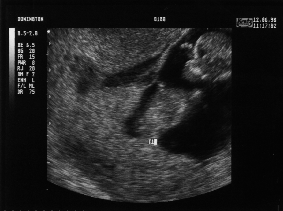

11 Weeks - Friday 12th June 1998 (Approx 50mm)

Eleven Week Scan 1

Twin 1 (Emma), head to top right, fingers of right hand visible by forehead, body lying diagonally.